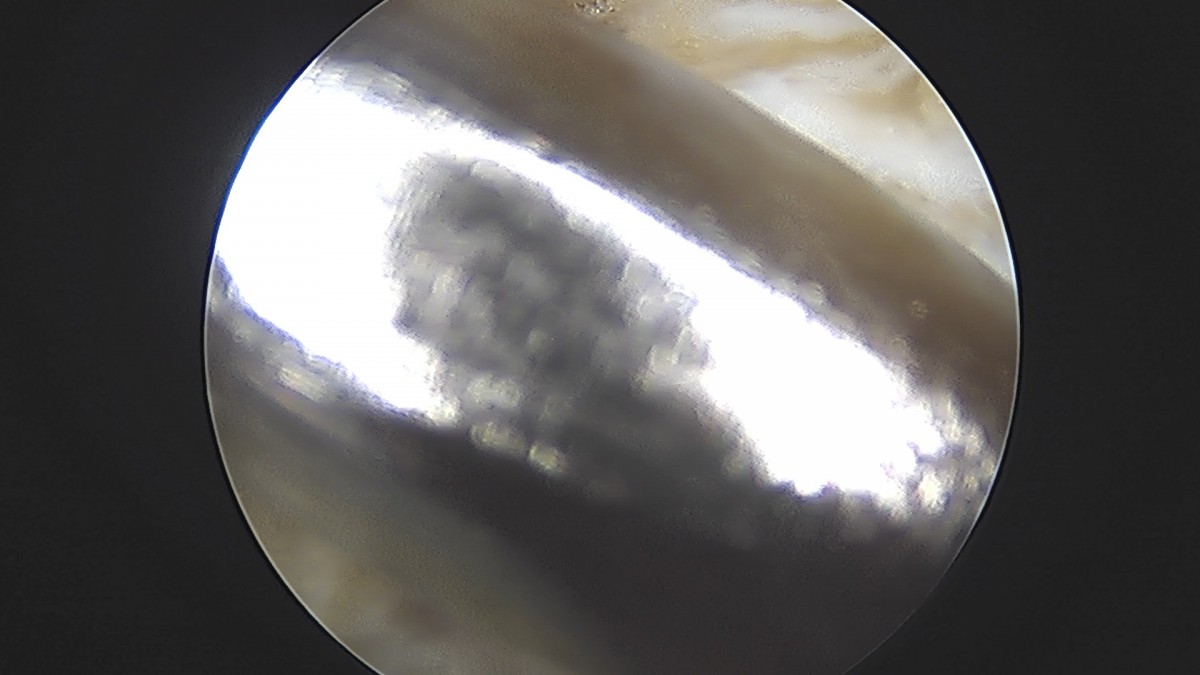

정지영원장님 무릎 반월상 연골판 절제술 이영O 환자

dae765e4d9ac96aee867c9d6292d8784_1758009376_5813.jpg